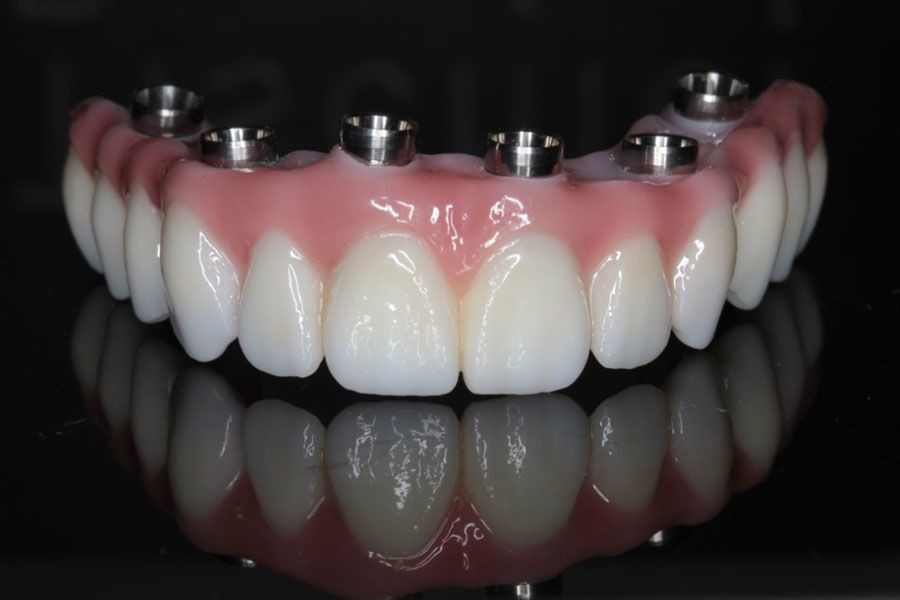

What Happens During a Full Mouth Reconstruction?

Has your general dentist told you that you need a full mouth reconstruction to restore your teeth and smile? This is an important procedure for your health and the aesthetics of your teeth. You will likely go into your procedure with some questions and concerns. It is helpful to understand what will take place at the dentist’s office and what the results will look like. You can rest at ease knowing that there are many benefits to repairing damaged teeth and replacing missing ones.

Issues that lead to the need for full mouth reconstruction

Everyone should have a goal of maintaining healthy, strong teeth, and gums. Unfortunately, some people neglect these duties or do not attend to them effectively. People who experience tooth loss or damage can often trace these issues back to brushing and flossing. Failing to do these things each day can lead to decay and infections. These conditions can weaken teeth, causing cavities, fractures, and cracks. A tooth could even fall out or require extraction.

Accidents and injuries can also break or chip a tooth. A hard enough blow to the face or biting into an object can even dislodge a tooth. Tooth loss and damage can occur in a car collision. These issues can also happen while an individual is playing sports.

Preparation

Before starting full mouth reconstruction procedures, the patient will meet with the general dentist. The dentist will explain the upcoming process and outline how it will affect the patient’s smile and health. The person should ask any questions they have. This is also a good time to address concerns and ask about any potential side effects the procedure may have.

After the consultation, the dentist will do some preparatory work. This will include taking X-rays and making impressions of the mouth. This information will be important in making devices, such as crowns, veneers, bridges, implants, or dentures. Before a dentist can start treating the patient’s condition, tooth extraction may be necessary.

Making the patient comfortable

A full mouth reconstruction procedure will require numbing the mouth. The dentist will do this so the patient will not feel pain during the process. This happens with a local anesthetic that should wear off a few hours after the appointment. Some dental offices offer sedation or other methods to calm the patient.

Preparing the tooth

Some full mouth reconstruction procedures require work on the tooth before the dentist places the device. For crowns, the dentist must first reshape the tooth by shaving part of it off. This helps ensure that the cap will fit. For veneers, the dentist first removes a bit of enamel and roughens the tooth so the veneer will bond to it. If the patient is getting bridges, the dentist will first place crowns over the teeth adjacent to the gap in the mouth.

Prepare for your appointment

You do not need to feel overwhelmed for your full mouth reconstruction. These processes are involved but can have successful outcomes. Review these guidelines so you can feel ready when you visit the dentist. Start by talking to the dentist about whether a restoration makes sense for you.

Three Misconceptions About Dental Implants

If you have chosen to have dental implants inserted to fix a dental issue, or are still researching and picking the best option for you, then today we will look at some of the misconceptions about dental implants. Unfortunately, there are many surrounding the topic of dental implants, and today we will focus on three.

Top 3 misconceptions about dental implants

With dental implants becoming more popular as a solution for different dental issues, we will set the record straight about the top three misconceptions regarding dental implants.

Misconception #1: People will notice that I have dental implants, and it could make me self-conscious.

One reason that dental implants have become so popular is because of their visibility in the mouth. Most people who have suffered from teeth loss in the past were only given options that were quite noticeable when they were installed. However, with dental implants, people are given the option of having teeth restored using a device and solution that is not noticeable at all. Most people who choose dental implants and do not tell new acquaintances would never even know that they had implants.

Misconception #2: The cost of dental implants is not worth it, or I would never be able to afford it!

One thing that many people do not realize when they see the cost of dental implants is the long-term benefits. This also relates to the long-term expense of a solution to lost teeth. When compared to another popular tooth replacement solution like dental bridges, dental implants are still the most cost-efficient choice when it comes to restoring missing teeth.

Misconception #3: Dental implants are uncomfortable or do not feel very good.

Again, this is far from the truth when it comes to dental implants. Many people that have dental implants inserted have commented after the procedure and after all of the healing that it is far less painful than they ever imagined any solution to replacing missing teeth would be.

When it comes to dental implants, they look and feel like a natural tooth because of how they are constructed and inserted into the jawbone.

Dental implants are one of the best solutions people can choose. The other benefits include stimulation of the nerves and jawbone. This also leads to no other issues with having your outward appearance affected years down the road from deterioration of the bone.

Are there other misconceptions?

There seem to be a lot of misconceptions regarding dental implants. This includes misconceptions about recovery time and the maintenance after installation. Most dental professionals and dentist nowadays agree that dental implants are one of the best (if not the best) solutions for people who have lost a tooth or multiple teeth and are looking to restore and fill those gaps.

One of the best ways that you can learn all there is to know about dental implants is to speak to your dentist and be open and honest about what questions you have. They will also be happy to help with any reservations that you may be thinking about when choosing between dental implants or other restorative dental options.